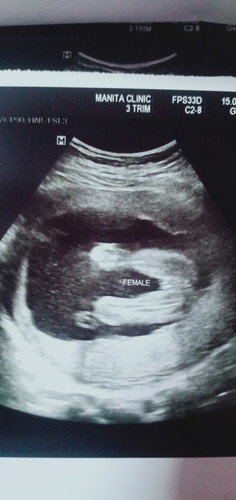

แม่ๆช่วยดูหน่อยนะค่ะ ผช.รึ ผญ หมอยังไม่แน่ใจค่ะ ขอบคุณนะค่ะ

กลีบชัดมากแม่ สาวแน่นอน เหมือนของเราเลย